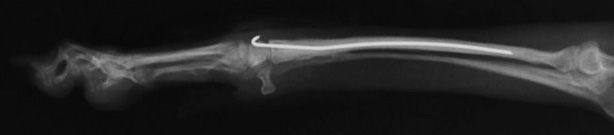

両前肢の骨折:橈骨尺骨骨折整復手術②

手術前レントゲン写真①

手術後レントゲン写真①

手術前レントゲン写真②

手術後レントゲン写真②